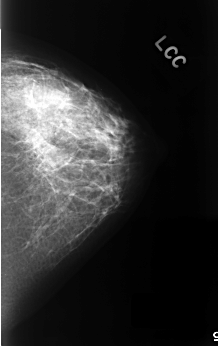

C_0330_1.LEFT_CC

LEFT_CC LINES 4496 PIXELS_PER_LINE 2824 BITS_PER_PIXEL 12 RESOLUTION 50 NON_OVERLAY